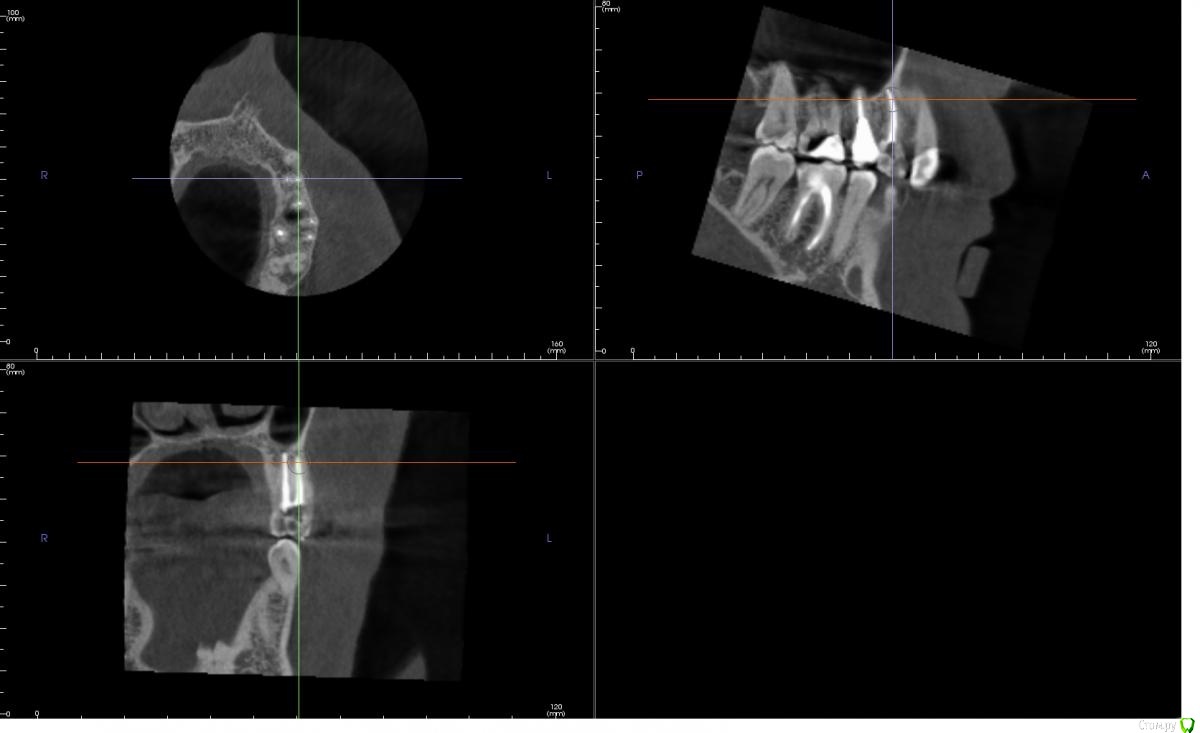

andreymir Опубликовано 7 марта, 2021 Поделиться Опубликовано 7 марта, 2021 Было проведено лечение каналов из-за кисты на 24 зубе. 2 канала, 2 корня. На КТ каналы запломбированы, но между каналами на всем протяжении каналов прослеживается затемнение. В описании, ранее сделанного КТ (в процессе лечения) рентгенологом указано, что корни срослись (каналы?) на всем протяжении. Затемнение между каналами на всем протяжении зуба на ранее сделанном КТ, к которому было приложено данное описание, не прослеживается. Это затемнение обнаруживается только на КТ, выполненном сразу после лечения. Затемнение между каналами на последнем КТ выходит за границу зуба, за границу кости и сливается с синусом. Скрины с КТ прилагаю к данному сообщению.Вопросы:1. Что это за затемнение? Не мог же появится новый канал в процессе лечения? Или это не заполненная пломбировочным материалом часть канала? Или это полость, которая соединяет каналы на всем протяжении?2. Верно ли, что раз затемнение выходит за границу зуба, то это означает, что стоматолог "перестарался", проткнул кость и провалился в синус? И теперь через весь зуб проходит не заполненный пломбировочным материалом канал связанный с синусом?3. Что делать с таким зубом? Можно ли ставить коронку, его нужно перелечить или он безнадежен и его пора менять на имплант?Спасибо!КТ ниже выполнено сразу после ЗАВЕРШЕНИЯ леченияКТ ниже выполнено в ПРОЦЕССЕ леченияЕсть КТ до начала лечения, если необходимо могу приложить в следующем сообщенииХорошего дня! Ссылка на комментарий

andreymir Опубликовано 7 марта, 2021 Автор Поделиться Опубликовано 7 марта, 2021 (изменено) у вас все нормально, не ищите проблем там где их нет. Зуб восстанавливайте искусственной коронкойБольшое спасибо вам за ответ, но я был бы вдвойне признателен за более обстоятельный ответ. Меня слегка тревожит первое изображение. Можете уточнить, что за затемнение проходит через весь зуб между двумя каналами на первом изображении и выходит в синус? Спасибо! Изменено 7 марта, 2021 пользователем andreymir Ссылка на комментарий